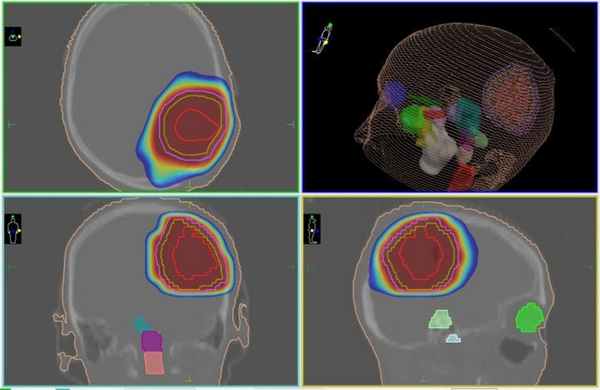

![Цифровой трехмерный план лечения глиобластомы на линейном ускорителе]()

Цифровой трехмерный план лечения глиобластомы на линейном ускорителе

![План лечения глиобластомы на КиберНоже (радиохирургия)]()

План лечения глиобластомы на КиберНоже (радиохирургия). Внутри зоны, очерченной красным цветом будет сформирована высокая доза ионизирующего излучения, губительного для клеток опухоли

Безопасность лечения глиобластомы обуславливается точным выявлением границ опухоли и взаимного расположения здоровых тканей головного мозга, проводимым определяется перед началом лечения методами КТ и МРТ с последующим построением пространственной 3D-модели, по которой мощный программный комплекс рассчитывает параметры подачи каждого из множества тонких пучков ионизирующего излучения, из которых и будет сформирована общая доза в опухоли.

Во время сеанса лечения система слежения КиберНожа сверяет с заранее сформированным планом лечения положение опухоли перед подачей каждого из пучков излучения, что сохраняет точность даже в случае движения пациента, минимизируя облучения здоровых тканей, окружающих опухоль головного мозга.